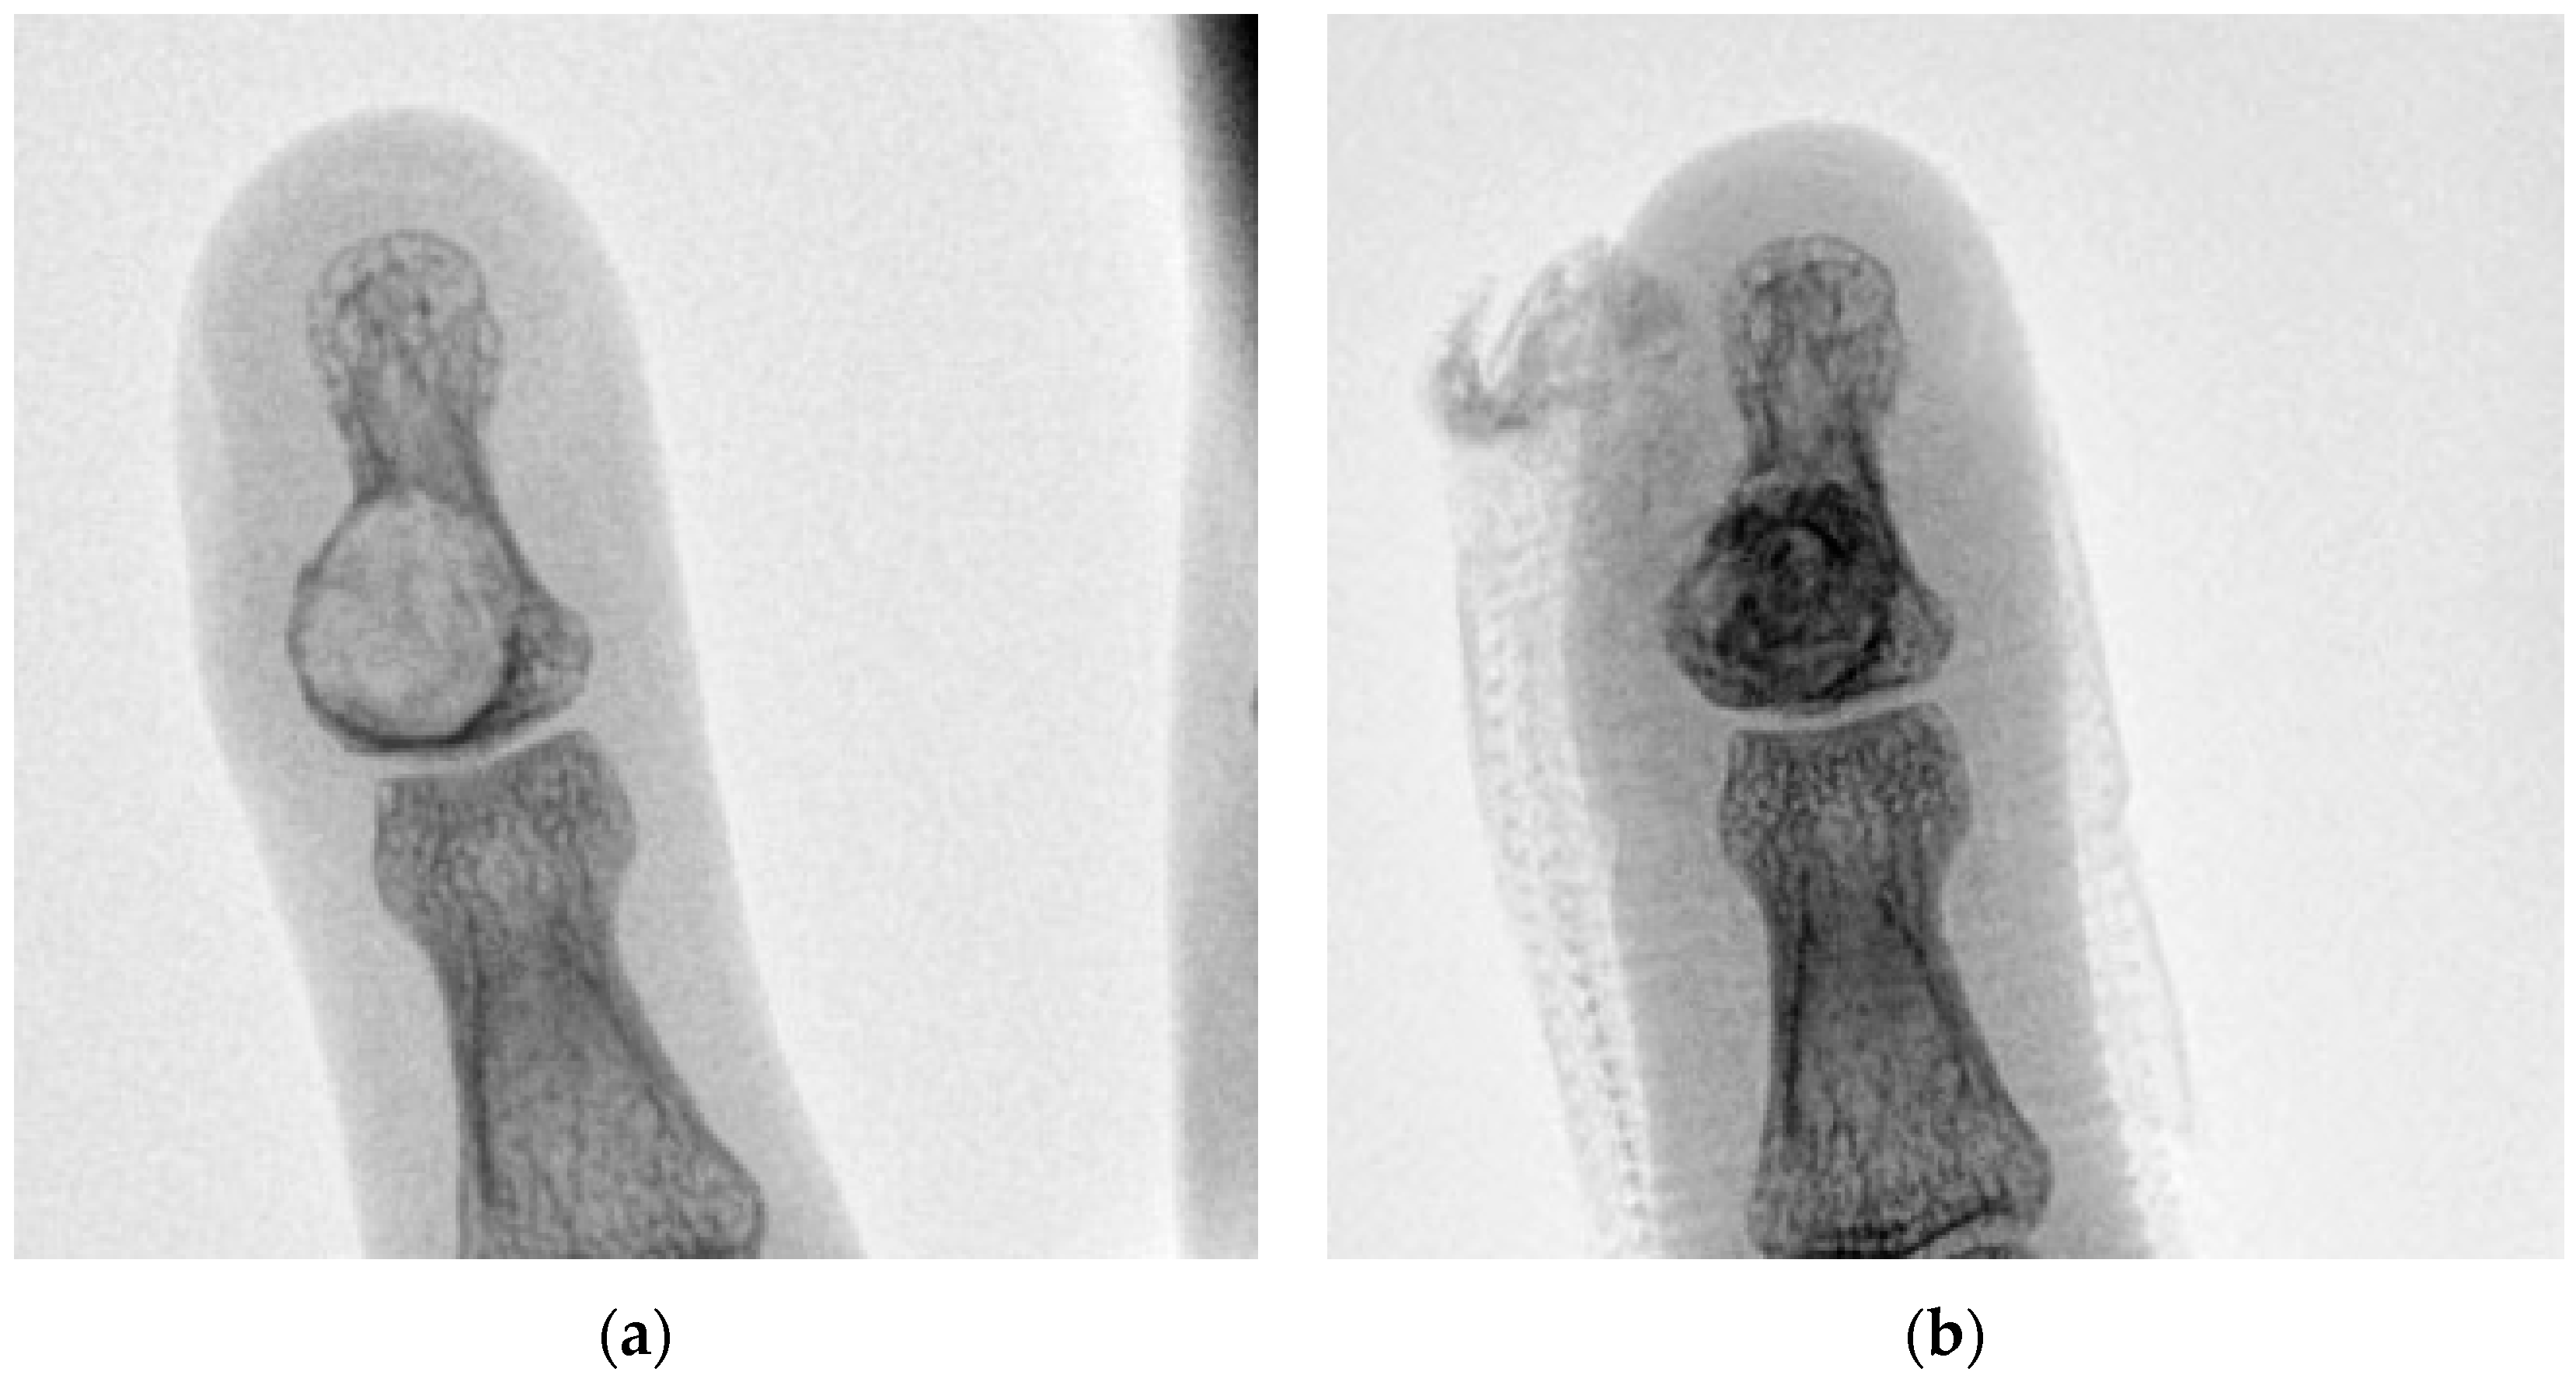

| 5 | 36 M | 1 | Left little finger P3 | 10 | Enchondroma | 25 |

| 7 | 71 M | 2 | Right middle finger P3 | 20 | Epidermoid cyst | 27 |